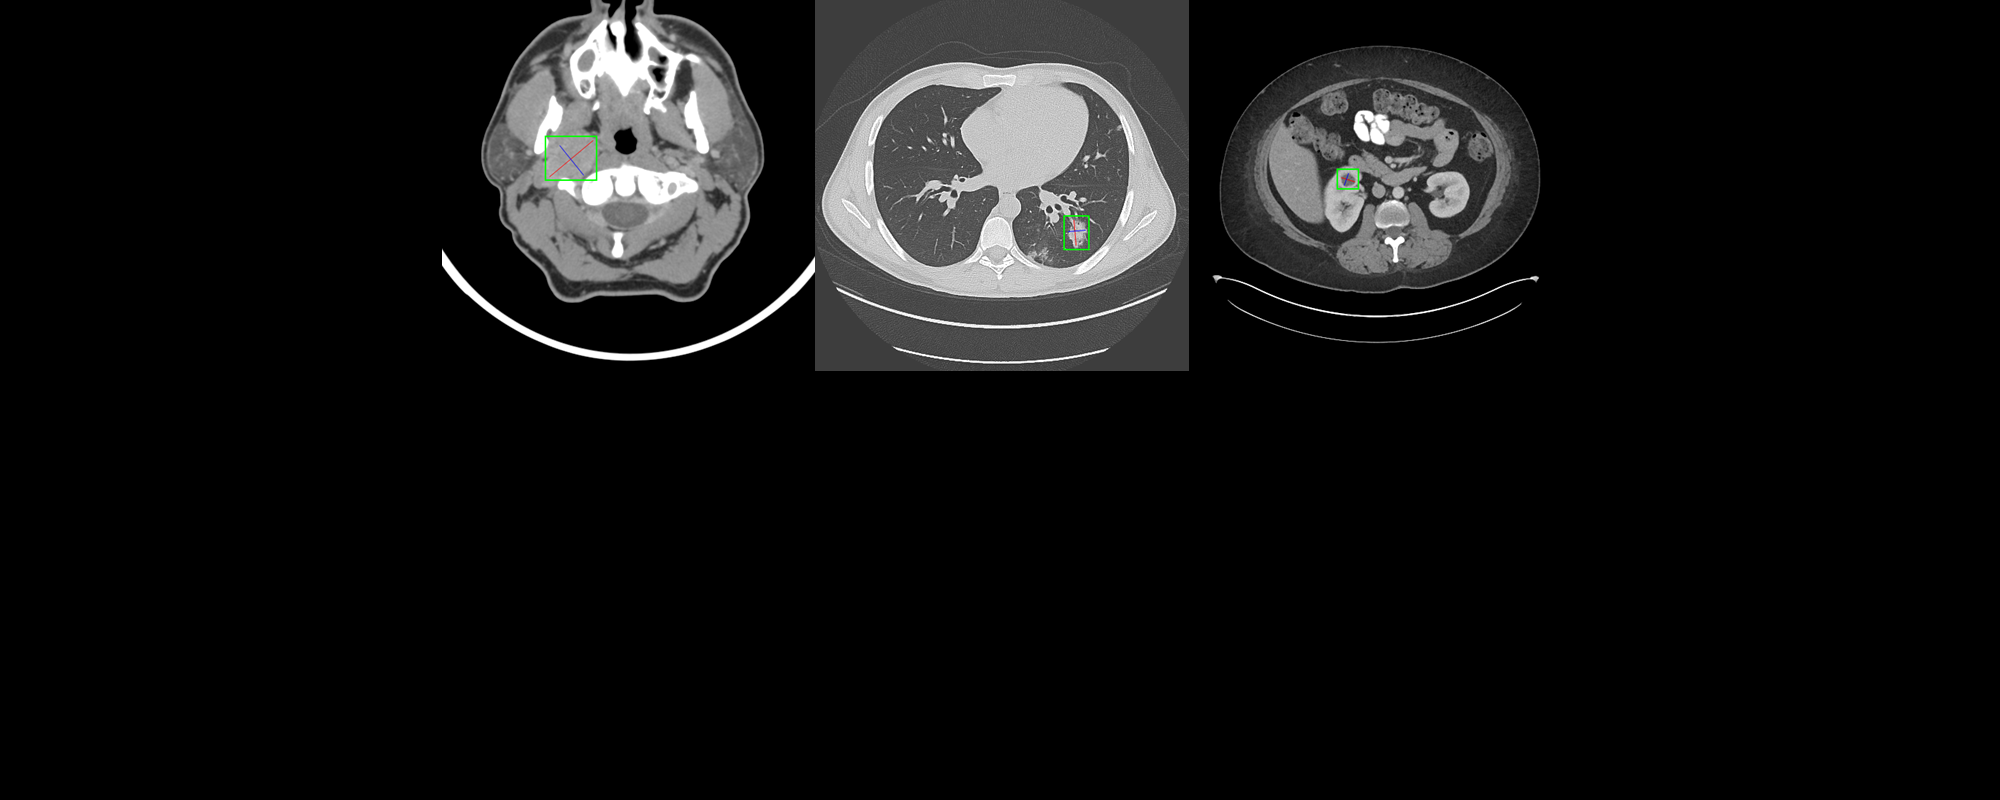

美國國立衛生研究院(NIH)公開擁有32,000張電腦斷層掃描(Computed Tomography, 簡稱CT)影像的大型成像資料庫,稱為DeepLesion,資料來自NIH臨床中心(Clinical Center)4,400多名病患。不同於目前公開的病變醫學影像資料庫,僅能偵測單一類型病變,DeepLesion涵蓋範圍為全身,如肺結節、肝腫瘤、淋巴結腫大等。

請使用下載的資料庫與灰階CT影像,建置用於偵測病變位置的模型,位置共有8種,分別為:

Bone—骨頭

Abdome—腹部

Mediastinum—縱膈

Liver—肝臟

Lung—肺臟

Kidney—腎臟

Soft tissue—軟組織

Pelvis—骨盆